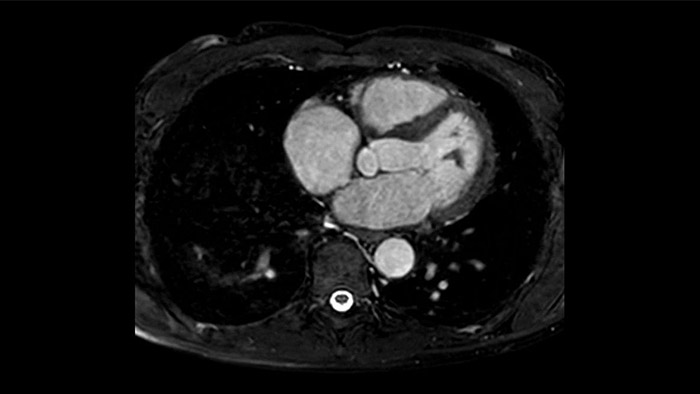

A utilidade do diagnóstico e prognóstico da RM cardíaca está a aumentar. Avalie a anatomia e função do coração utilizando aquisições cine, adquira informações sobre a perfusão e viabilidade do tecido cardíaco, visualize potenciais edemas com sequência de sangue escuro, aceda e quantifique mesmo a caracterização do tecido com a CardiacQuant.

IntelliSpace Portal MR Caas7,8 A solução de pós-processamento 4D Flow permite a geração de reconstruções de volume 3D, para visualizar e avaliar o fluxo sanguíneo em estruturas cardiovasculares, incluindo válvulas cardíacas, câmaras e vasos, com base nas imagens de RM 4D Flow cardiovascular.